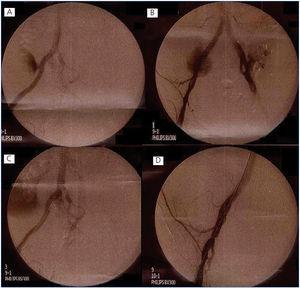

Ante estos hallazgos, se decidió llevar a cabo la reparación urgente de éste. Bajo anestesia local y sedación, se implantó una endoprótesis Viabahn® en la arteria ilíaca común derecha, extendiéndose a la arteria ilíaca externa. En el control angiográfico se observó la exclusión del pseudoaneurisma con oclusión de la arteria hipogástrica. Se completó el procedimiento con la colocación de un stent Visi-Pro® distalmente a la endoprótesis debido a un defecto intimal visualizado (figura 2). Fue dada de alta 8 días después, asintomática y con recuperación de su función renal basal.

Figura 2. Serie angiográfica